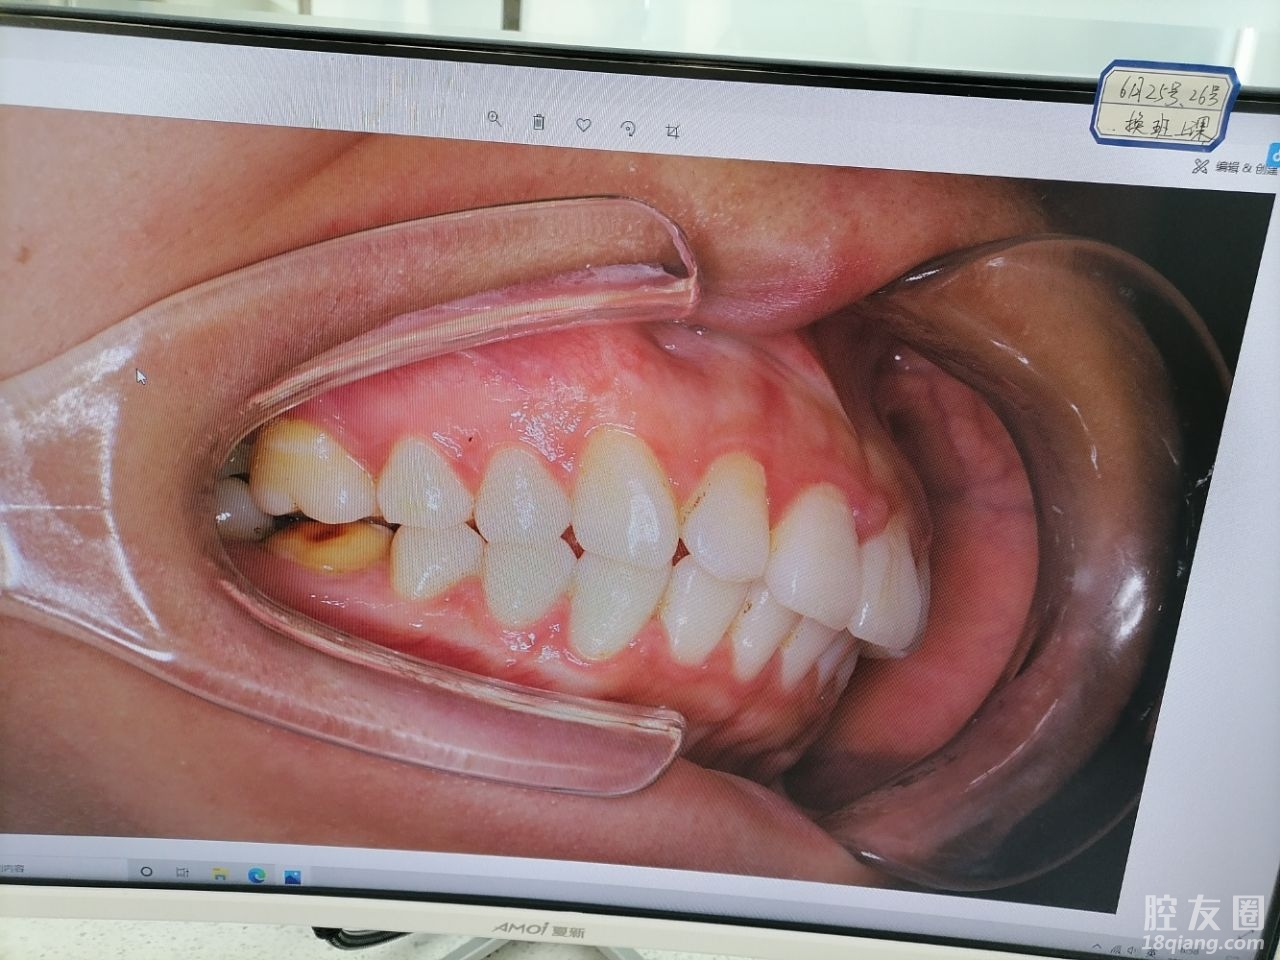

大学的时候带了钢牙套一年半了,后来因为保持器没有坚持戴,现在工作了时隔太久感觉又反复了,2021年决定彻底改变一下自己,算是给自己的礼物。

第三,技术专业,服务一流。口扫+拍片子+出方案,当天就很满意交了定金,希望矫正成功。